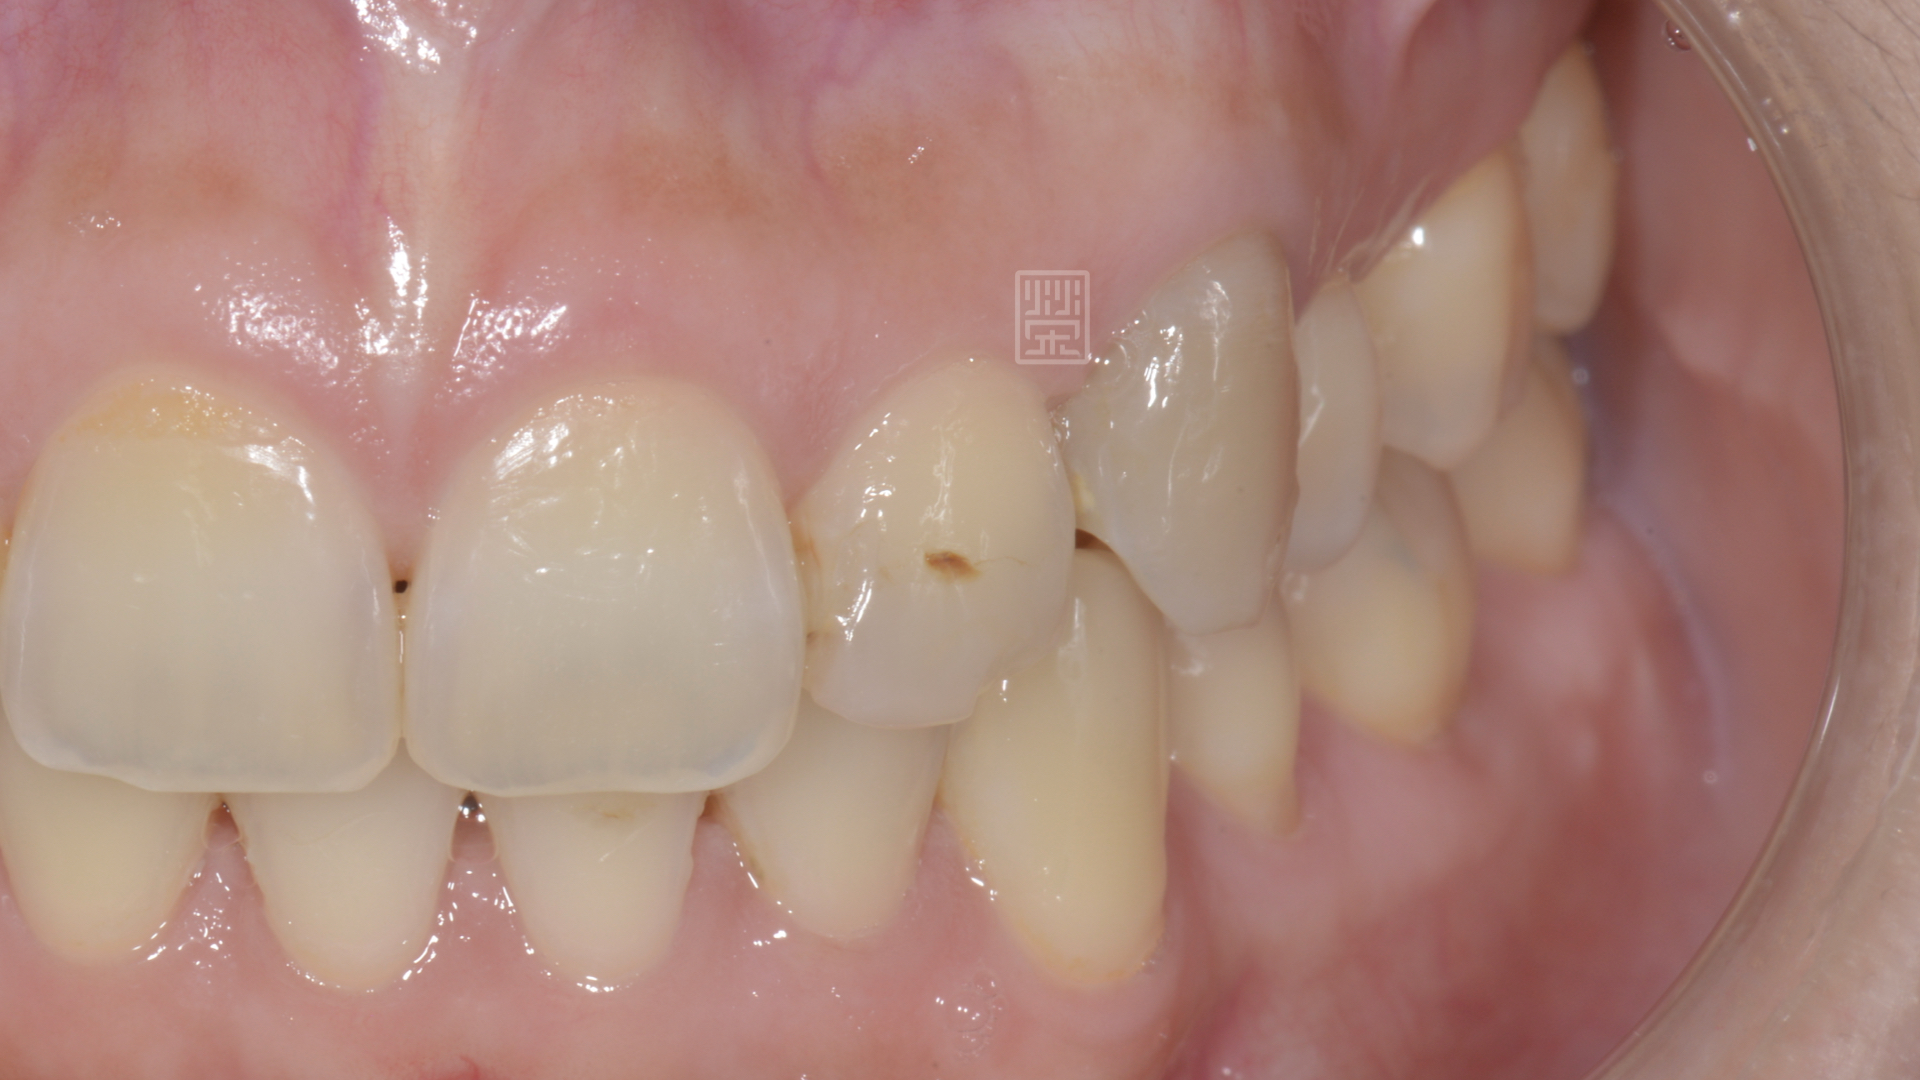

楊小姐市榮醫師多年的患者,有一天,突然來診說:我的牙齒變黑了!!

雖然牙齒顏色隨著牙釉質耗損,慢慢變暗,但是突然變暗這一定是有其他的原因,口內檢查,變色的犬齒並沒有蛀牙;但在X光片檢視下,發現牙齒根尖有黑色陰影,這表示牙齒神經已經病變壞死了,但這是為什麼呢?為什麼沒有蛀牙,牙齒神經也會受傷嗎?

犬齒變灰黑色